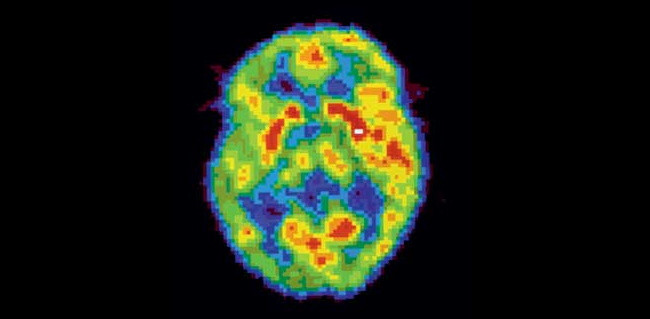

Активность мозга сильно различается не только во время бодрствования и сна — есть множество промежуточных состояний, которые можно различить во время позитронно-эмиссионной томографии.